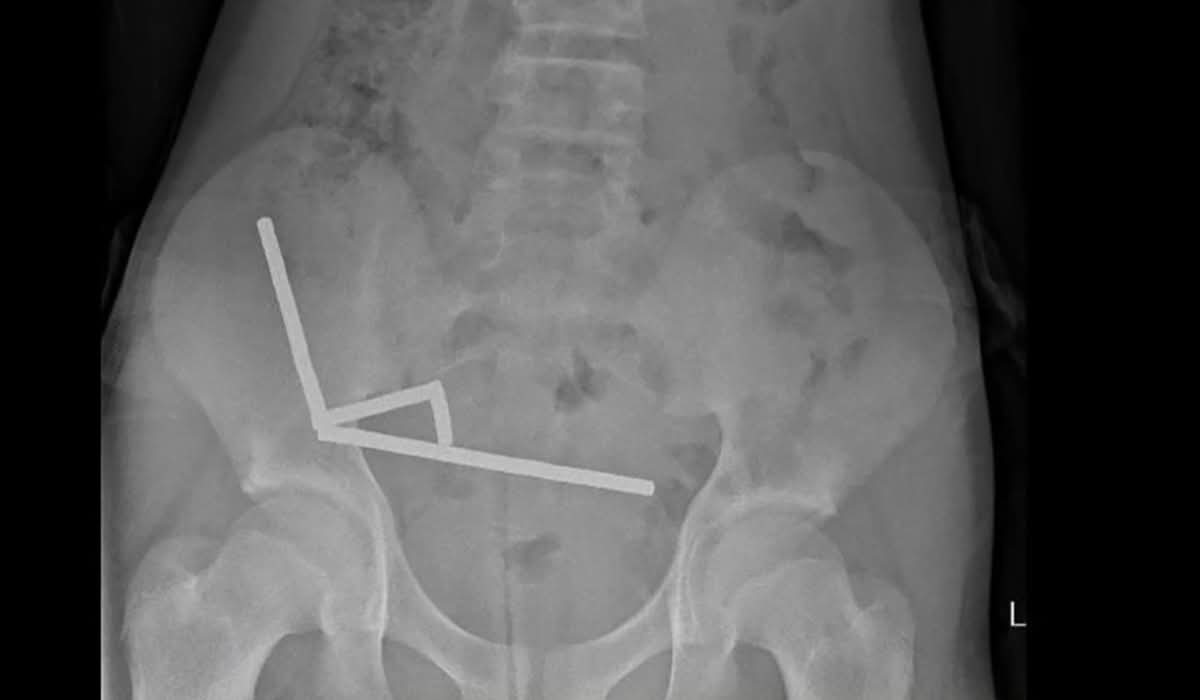

Un băiat de 13 ani din Noua Zeelandă a ajuns la spital după ce a înghițit între 80 şi 100 de magneți puternici. Acesta a aşteptat aproape o săptămână până să ceară ajutor medical, iar în cele din urmă a pierdut o parte din intestin, relatează CNN.

Potrivit CNN, băiatul a ingerat între 80 și 100 de magneți de tip neodim, fiecare având dimensiunea de 5 mm x 2 mm.